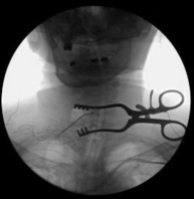

Se utilizó disección contundente y retractores de mano de Cloward para acercarse a la columna cervical anterior. Los gatitos se utilizaron para barrer la fascia prevertebral. Se colocó una aguja espinal en el interespacio C5-C6. La unidad de brazo en C se cubrió estérilmente, se llevó al campo y se usó para confirmar el nivel.

Bovie monopolar se utilizó para exponer la columna cervical anterior de C4 a C6 socavando los músculos coli largos bilaterales. Se colocó el sistema de retractor autoretenedor TrimLine. Los pines Caspar de 12 mm se colocaron en los cuerpos vertebrales anteriores C4, C5 y C6. La retracción suave se aplicó primero a través de C5-6.